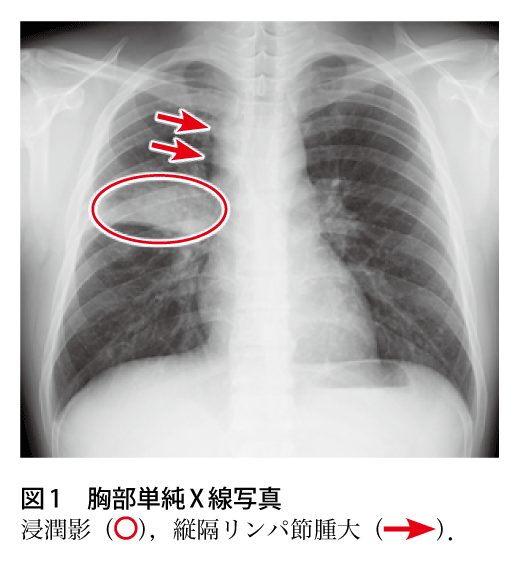

解答 解説 黄色痰 血痰を伴う咳嗽で受診した50歳代男性 実践 画像診断q A 羊土社 レジデントノート 羊土社